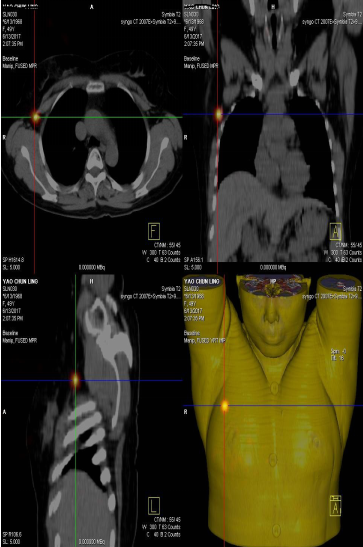

前哨淋巴結顯像技術一般在腫瘤附近注射放射性核素標記特殊藥物,這種藥物會被前哨淋巴結攝取,存在于前哨淋巴結中。24小時之內(nèi)都可用SPECT-CT進行前哨淋巴結顯像檢查。

患者李女士,發(fā)現(xiàn)右側乳腺腫物,來我院就診,行乳腺腫物局部擴大切除術,術后病理回報:右乳腺浸潤性導管癌III級,伴原位癌。擬行右乳腺癌切除術,提檢前哨淋巴結顯像檢查,明確有無淋巴結轉移。